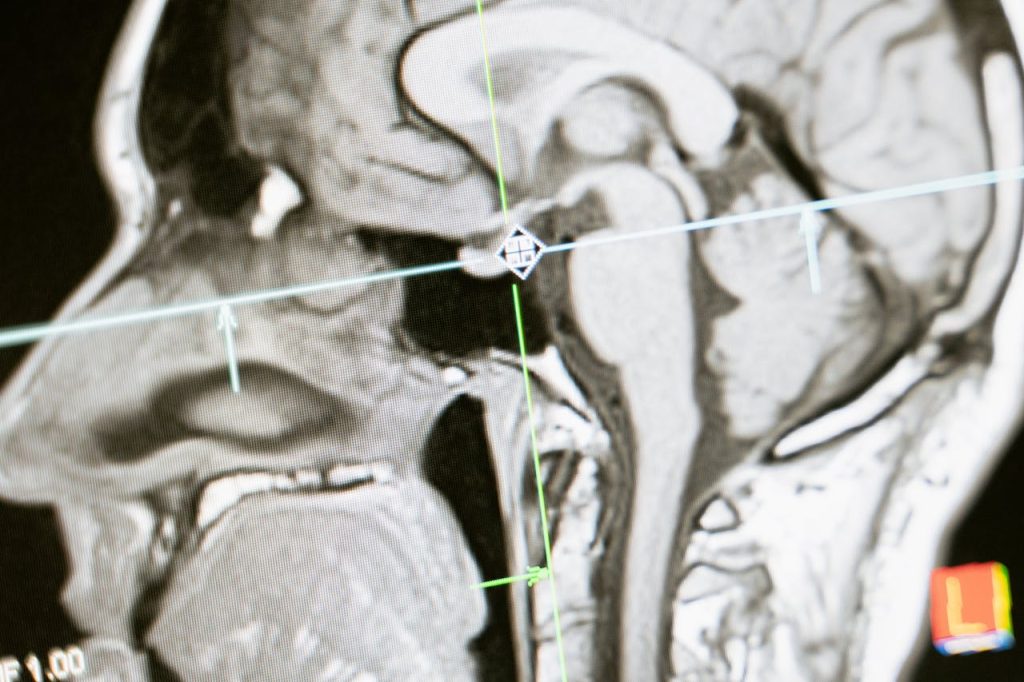

结合人工智能算法,影像系统可自动识别CT、MRI异常结构,辅助医生实现早期筛查与风险评估,提高诊断效率并缓解基层医疗资源紧张问题。

采用低剂量辐射设计与AI图像增强算法,提高图像清晰度,减少辐射风险,并布局便携式超声设备,推动基层医疗升级。